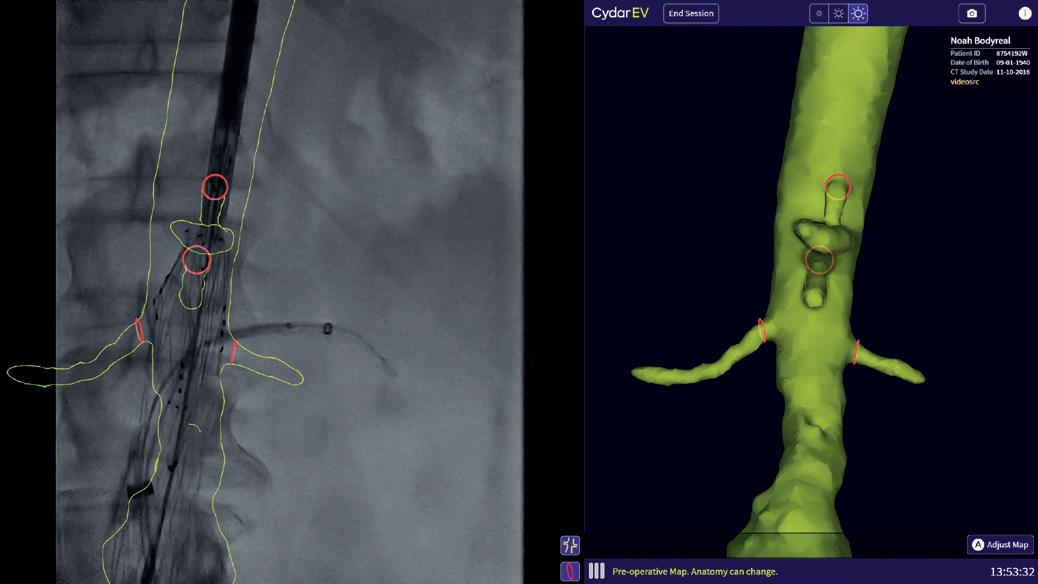

Image Tracking

The left image shows Image Tracking automatically overlaying the Map on the live X-ray fluoroscopy video on the left-hand side of the screen with a 3D rendering of the same Map on the right. The green color indicates that this is a Preoperative Map. The right image shows the same X-ray but with the Adjusted Map (blue color)

as a reference image. Image Tracking continues watching the live fluoroscopy on the left side until a new Map can be generated. When vessel deformation becomes apparent, for example with a digital subtraction angiography (DSA), the Cydar remote control can Adjust Map using Virtual Wires to straighten, bend, displace or rotate segments of the Preoperative Map to match the deformed anatomy.